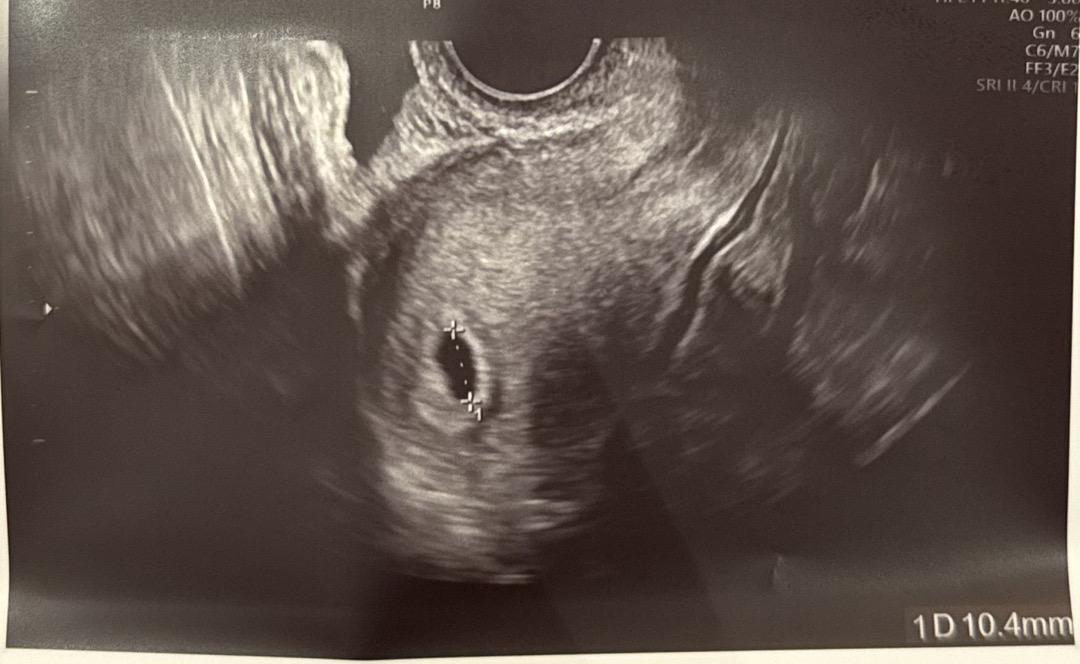

6주3일차 초음파 좀 봐주세요ㅠㅠ

오늘 초음파를 찍고왔는데 6주차에는 보통 난황이 보인다고 하던데 저는 아기집만 보이는것같은데ㅠㅠ 이런분들 혹시 있나요?? 5주차때 아기집이 0.34cm 였고 오늘 봤을때 1.04cm로 커지기는 했어요...